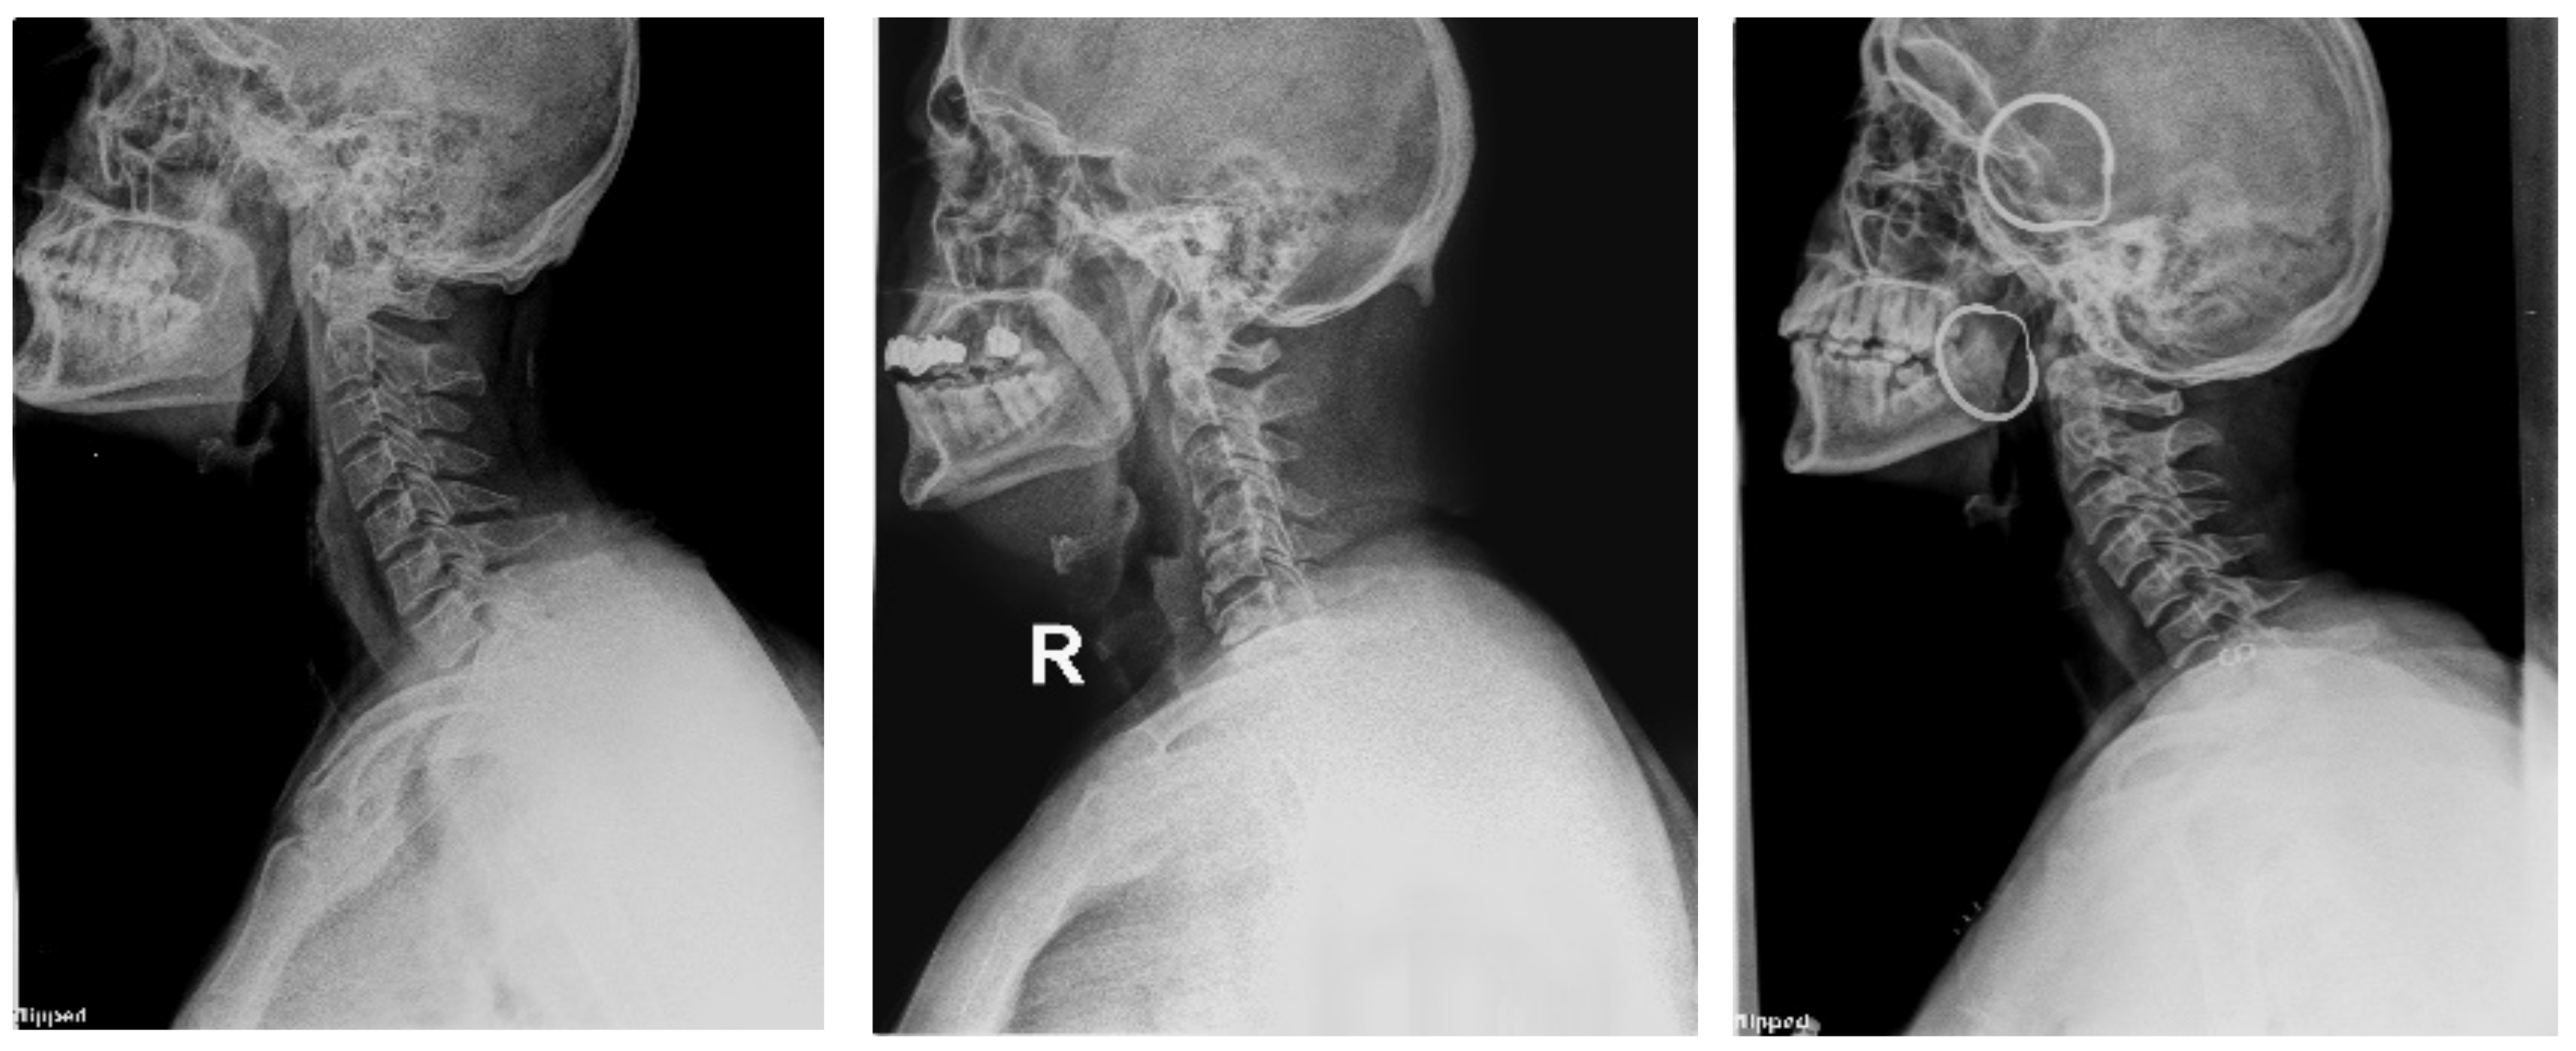

4.1.2. Clinical Case Study